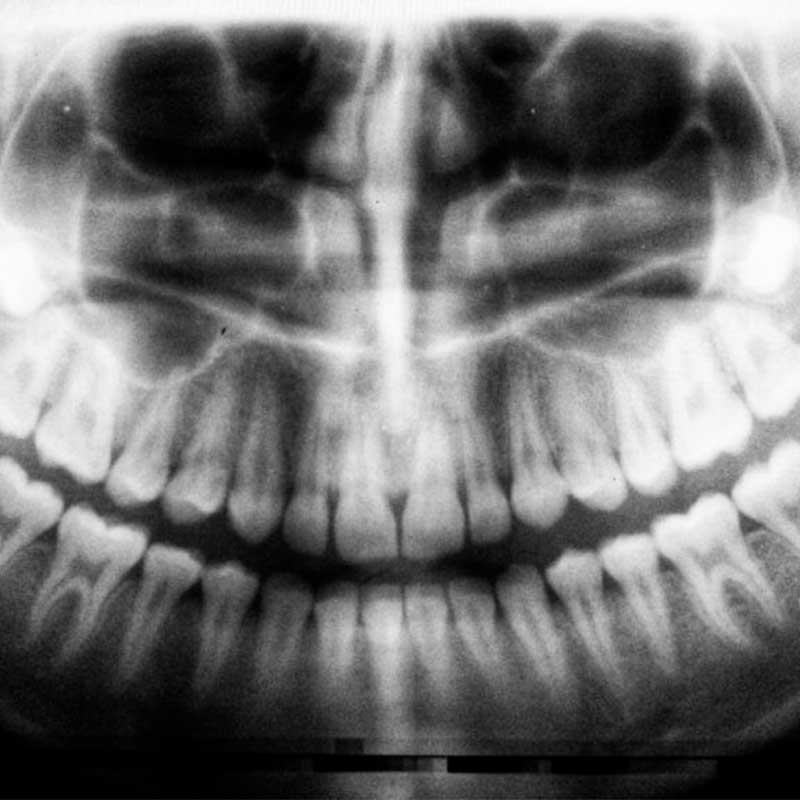

ORTODONZIA

L’ortodonzia mira a un sorriso armonioso e una salute orale ottimale mediante riposizionamento dentale personalizzato. Si basa su radiografie, impronte ottiche 3D e offre apparecchi fissi o mobili su misura. Disponibile anche l’ortodonzia invisibile con mascherine rimovibili, discrete ed efficaci